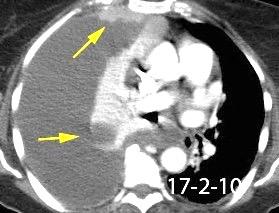

Absceso secundario a perforación de carcinoma. 3-4%. En flexura esplénica puede tener absceso subfrénico o empiema.

Empiema pleural secundario a carcinoma de la flexura esplénica (masa visible)

Lian R et al. Empyema caused by a colopleural fistula. Medicine (Baltimore) 2017/Osada T,, et al. Thoracic empyema associated with recurrent colon cancer: report of a case and review of the literature. Dis Colon Rectum 2001